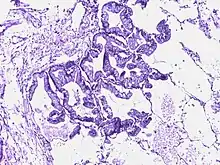

![]() | Bronchoalveolar carcinoma | Lepidic pattern of growth of tumor cells along the alveolar wall resembling butterfly sitting on fence. Normal alveoli is seen towards right side. | Category: Histopathology of bronchio-alveolar carcinoma | Bronchio-alveolar carcinoma |